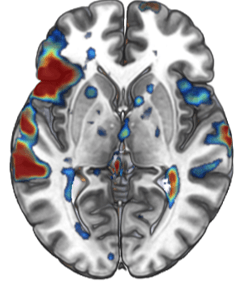

• Functional MRI (fMRI) analysis

• Task related activation mapping

• Resting state connectivity analysis

Sample fMRI activation map